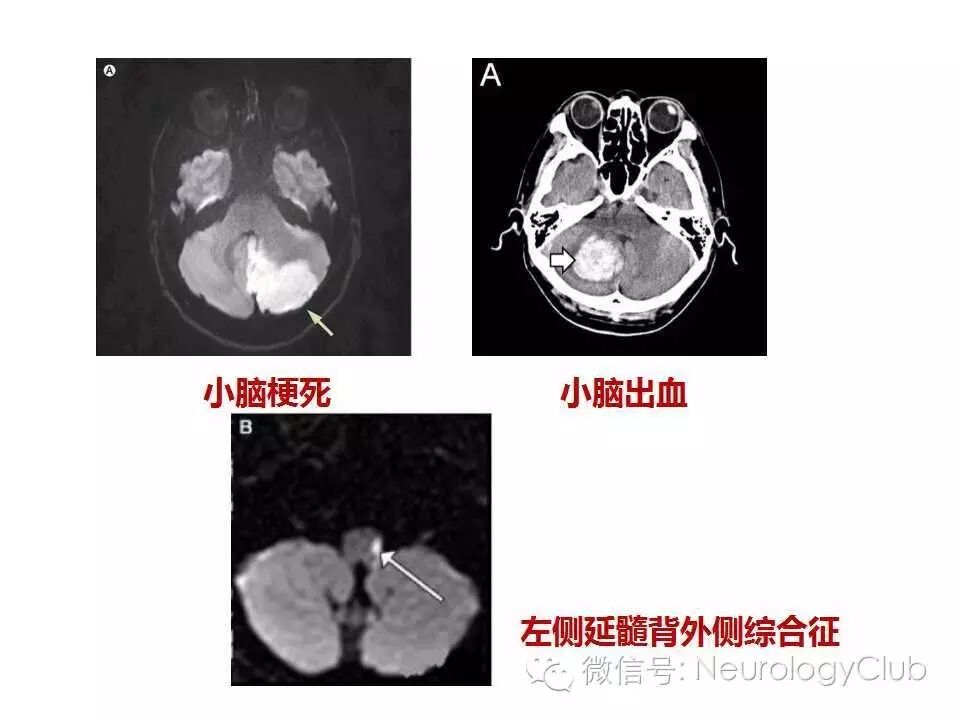

小脑性共济失调的鉴别诊断

共济失调是指小脑、本体感觉以及前庭功能障碍导致的运动笨拙和不协调,累及躯干,四肢和咽喉肌时可引起身体平衡、姿势、步态及言语障碍。小脑性共济失调是最常见的类型,主要症状包括姿势和步态异常,随意运动协调障碍(辨距不良,意向性震颤,写字过大征等),言语障碍(暴发性或吟诗样语言等),眼球运动障碍(眼震等),肌张力减低(钟摆样腱反射等)。